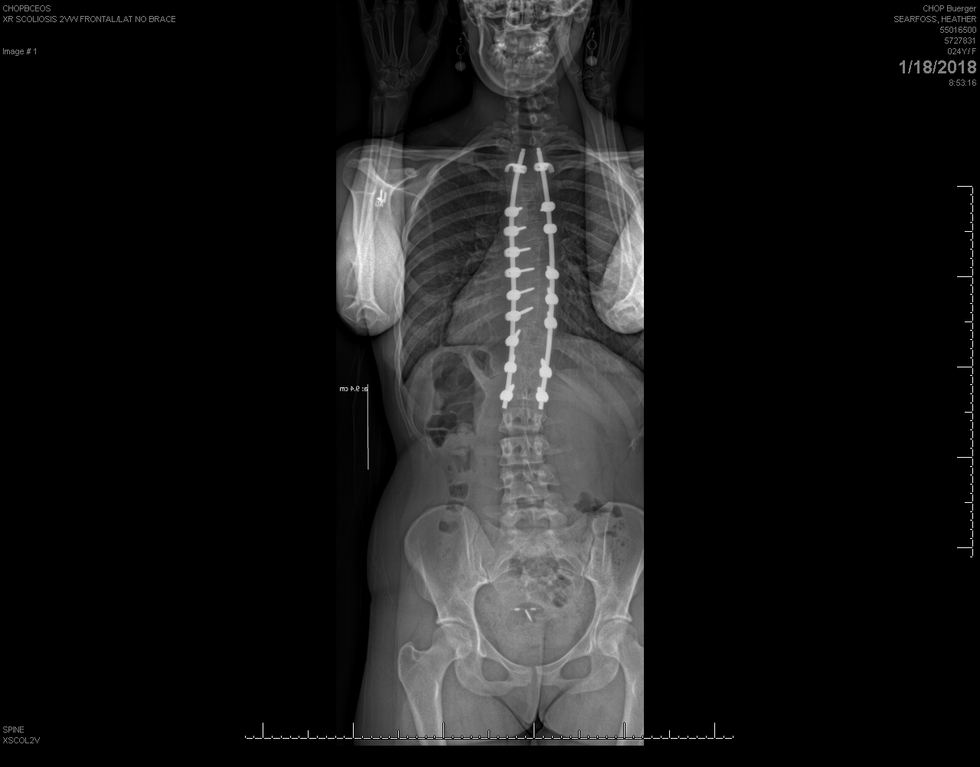

“Bracing will NEVER reduce the curvature, and surgery is only a temporary solution for scoliosis treatment” (2018 ST&RC) as for me, I have been through both treatments. I wore a back brace for 2 years and I had a spinal fusion on February 18th, 2008.

To this day, I still have the bars in my back from the surgery and my quality of life has improved since I was first diagnosed in the summer of 2004 so I would say this far I am lucky.